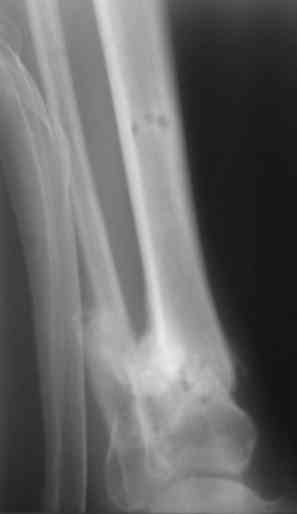

Уважаемые коллеги. 1.06.07 поступил солдатик, с огнестрельным сквозным ранением в н/3 левой голени. Огнестрельный перелом дистального отдела tibia. При поступлении АД 100/60. произведена обычная ПХО. Назначены антибиотики. Рана задренирована (пока что турунды с фурацилином). За последние сутки отмечался несколько раз подъем темп-ры до 38,5. Получает инфузионную терапию, цефазолин, линкомицин, добавили метрогил. Подскажите дальнейшую тактику ведения. И еще, что очень важно для нашего учреждения, возможные способы обезболивания при перевязке.

У меня сейчас лечится похожий пациент - ему стрельнули в упор из охотничьего ружья: открытый скозной перелом правой голени в н/3 с дефектом костной ткани до 6 см. При поступлении наложили ап.Илизарова. После отторжения всех некрозов и несмотря на сохраняющиеся раны (чтобы не терять время) мы провели повторную операцию - наростили аппарат Илизарова вверх на одно кольцо, под которым сделали поперечную остеотомию большеберцовой кости (в проксимальном метафизе) и теперь низводим образовавшийся промежуточный фрагмент по 1-2 мм в сутки при сохранении общей длины конечности. В месте остеотомии растет регенерат, который постоянно рентген-контролируем. Думаю что это самый лучший вариант для подобного рода травм. Если будет интересно могу показать снимки (как раз скоро очередной рентген-контроль).

3. Рентгенограммы